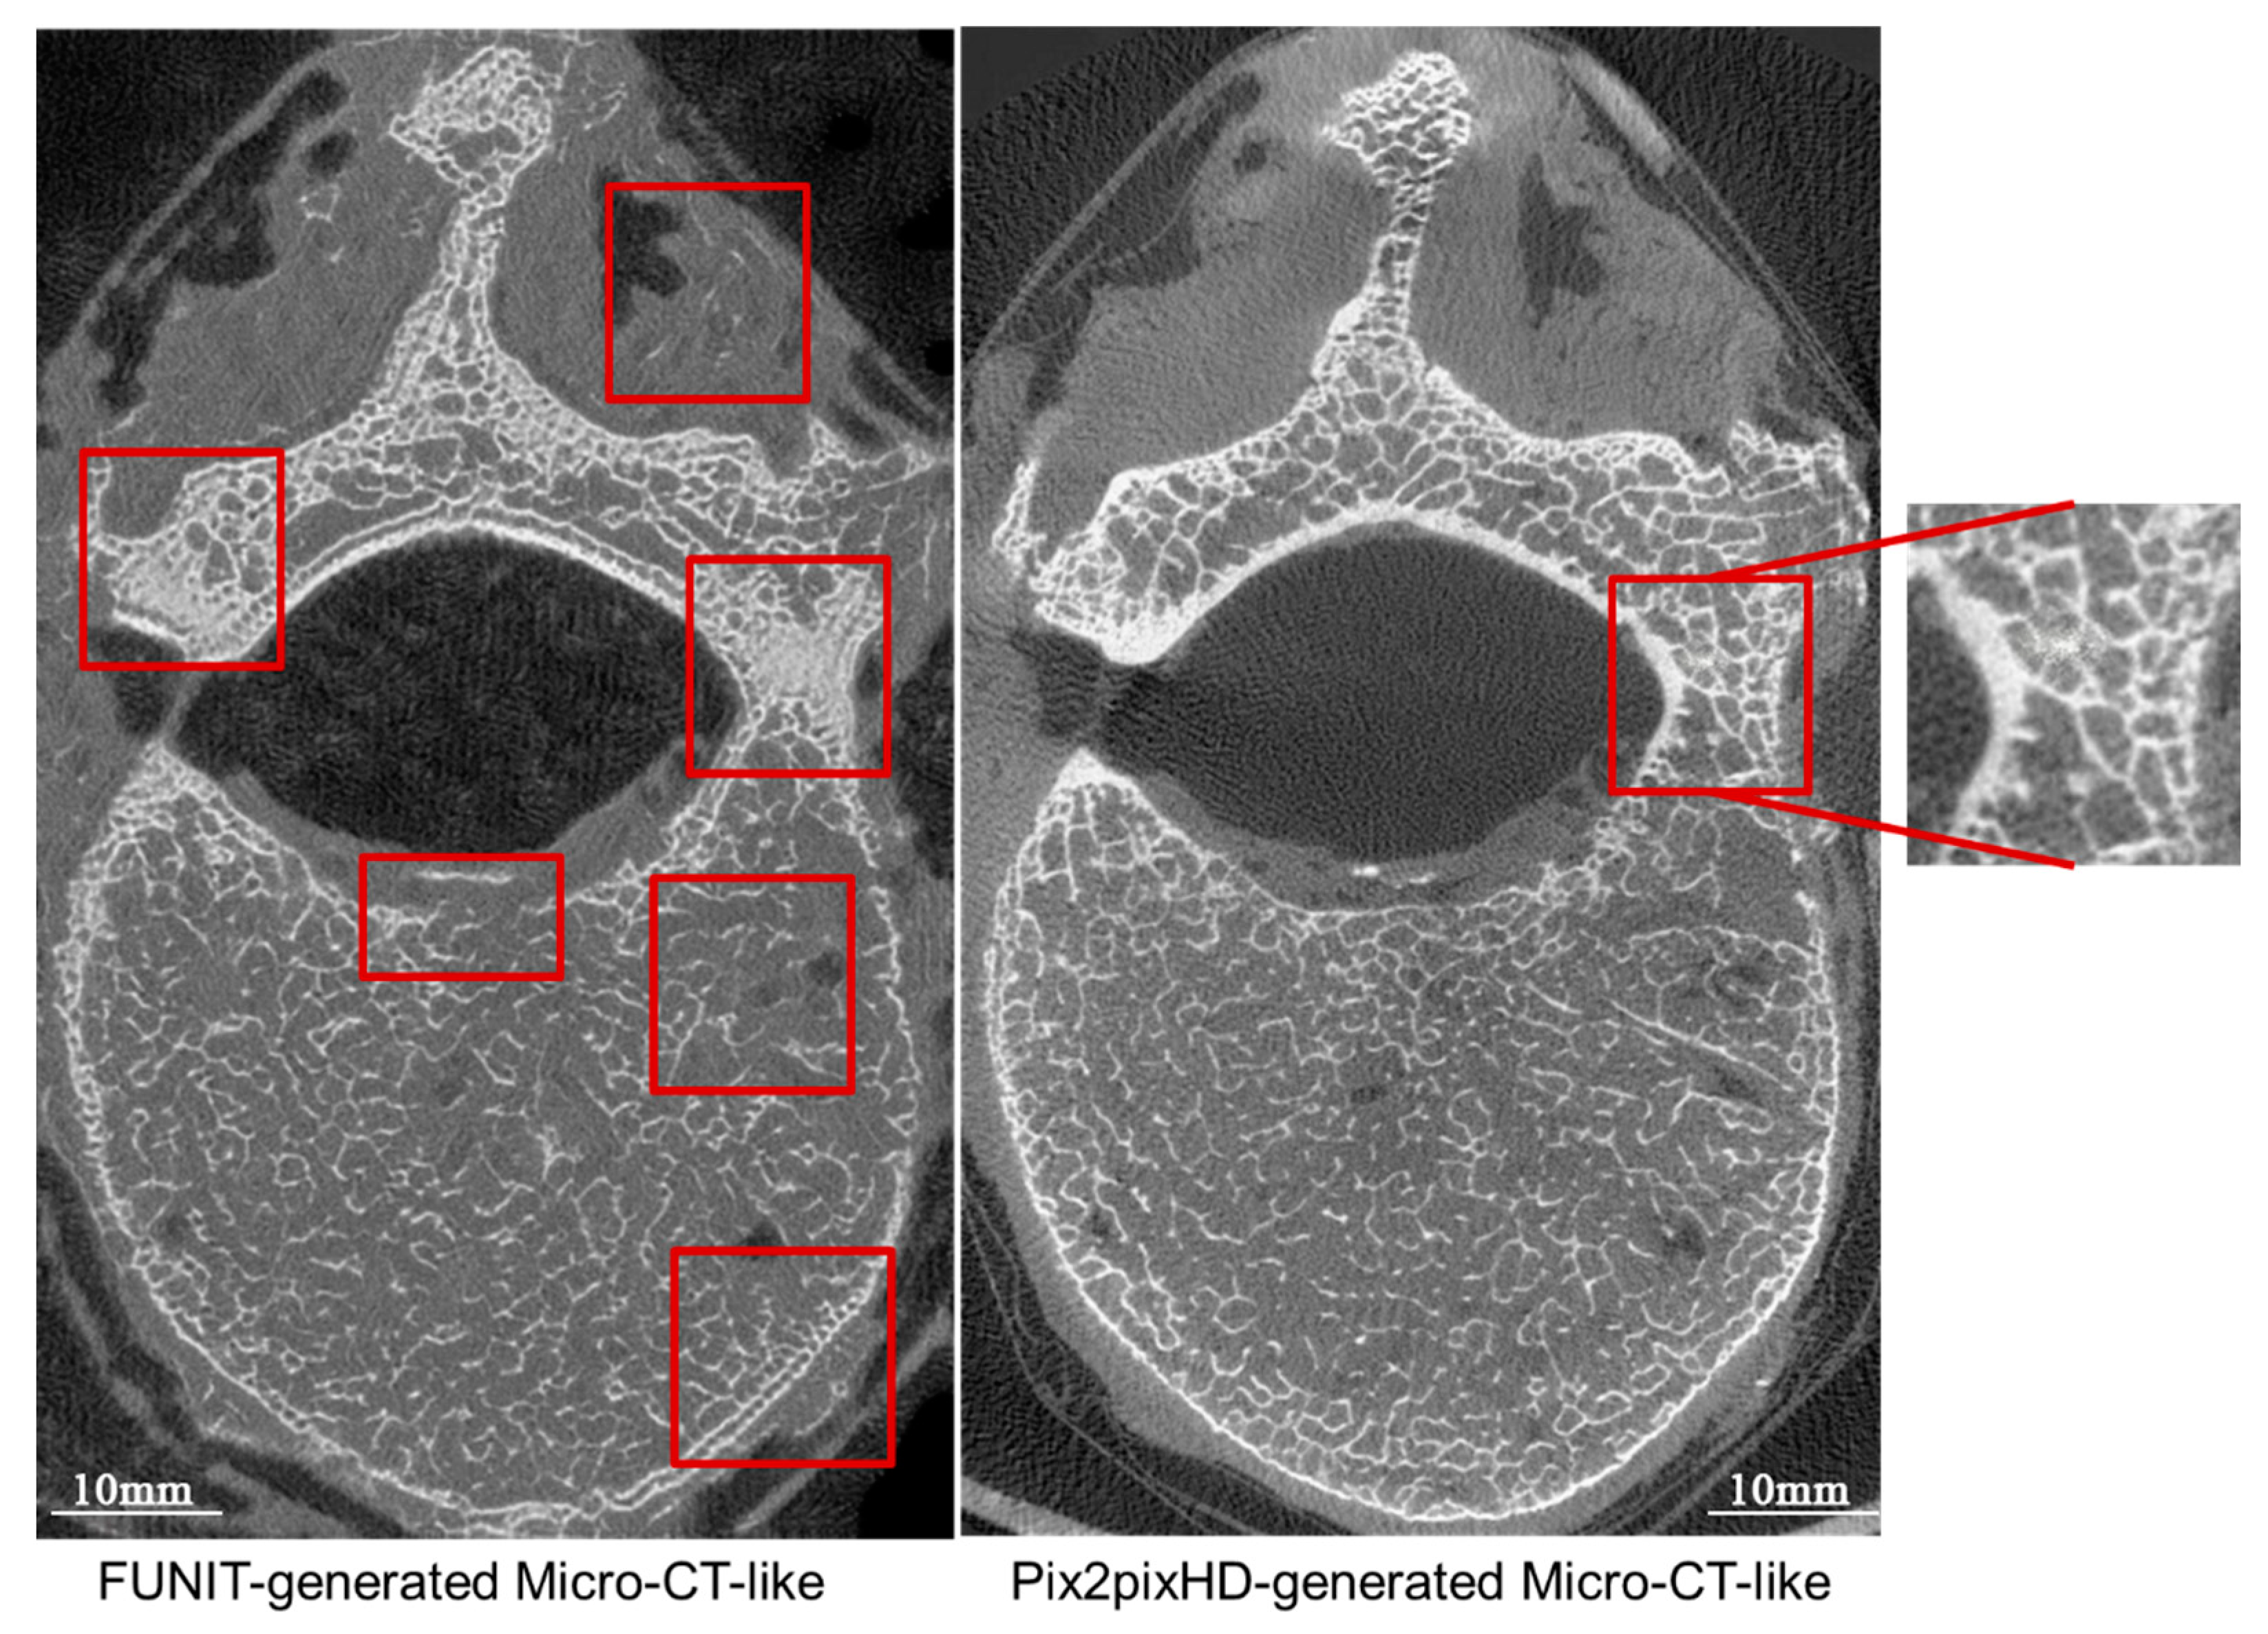

4.2.2. Comparison of Micro-CT-like Images Generated Using Unpaired-Image-Based FUNIT Model and Paired-Image-Based pix2pixHD Model

4.4.2. Paired-Image-Based pix2pixHD Model versus Unpaired-Image-Based FUNIT Model